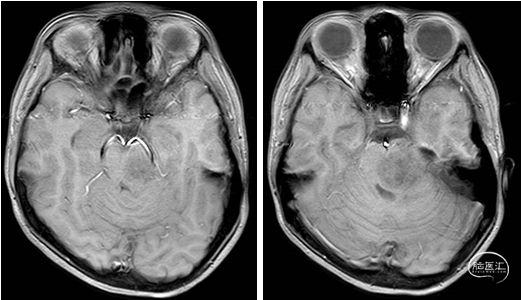

术前MRI

2023年9月13日 MRI T2

2023年9月13日 MRI+C